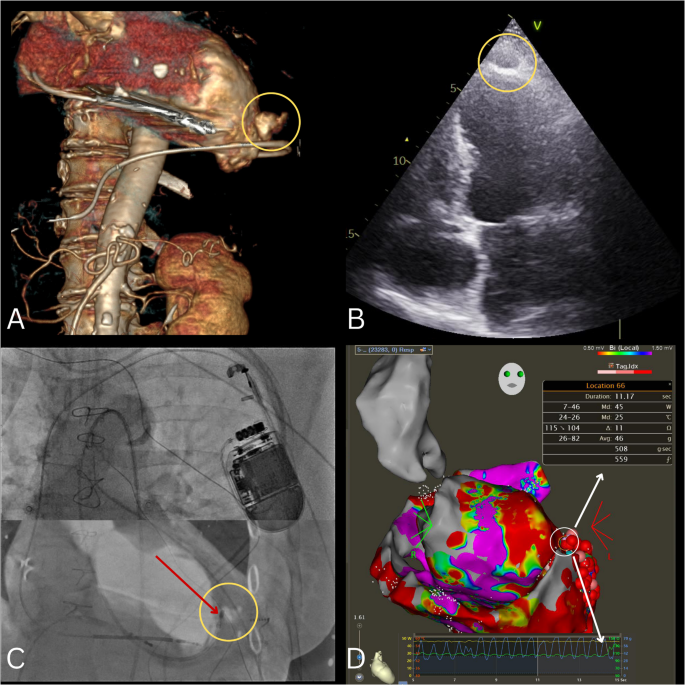

手术在全身麻醉下进行。在建立血管和心外膜通路后,使用高密度导管在右心室起搏过程中进行了电压和晚期激活映射(LAM)。由于术后粘连,大部分前心外膜区域无法触及。电压图显示左心室尖部、后部和前部存在一个大面积的低电压区域。LAM检测到各向异性的传导现象,存在减速区、晚期电位以及位于前间隔尖部的一个明显波前不连续线。为了进一步明确消融靶点,使用S3协议获得了另一张图谱[1]。冠状动脉造影排除了与主要冠状血管的邻近风险。心外膜消融采用3.5毫米的灌注式导管进行。随后将导管鞘更换为心包引流管,未观察到明显出血。在完成心内膜消融后不久,患者出现低血压,超声心动图显示有心包积液。引流出约300毫升血液后,血流动力学状况稳定。紧急进行的心脏计算机断层扫描(CCT)显示左心室前尖部有一个大的(35×25毫米)壁内血肿(图1A),超声心动图进一步证实了这一结果(图1B)。通过回顾荧光镜图像和电解剖图谱确认消融导管准确位于血肿位置(图1C)。在血流动力学崩溃前进行的最后一次消融操作显示出较高的接触力(峰值达82克)和突然的阻抗升高(图1D),因此立即停止了射频能量输送。